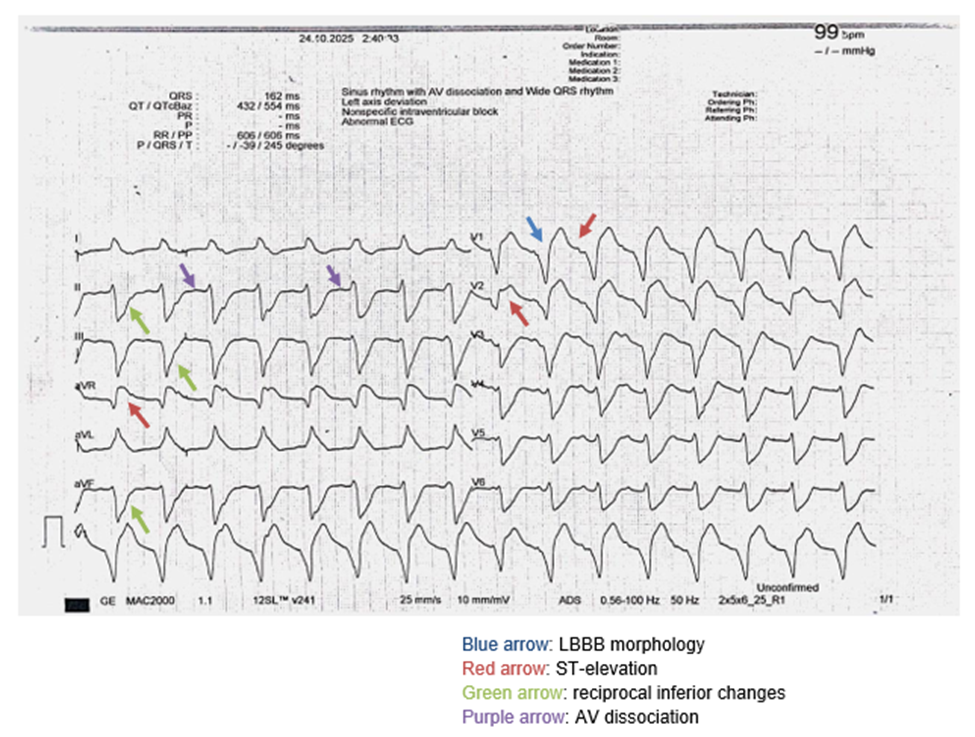

A 29-year-old woman without prior, significant medical history presented to the Accident and Emergency Department with acute onset of hemodynamic instability preceded by five days of viral prodromal symptoms of cough, fever, sore throat, and headache. Three days before admission the patient developed gastrointestinal symptoms including nausea, diarrhea, and vomiting, followed by acute retrosternal chest pain lasting for 30 minutes on the morning of presentation. Furthermore, the patient experienced a syncopal episode at home approximately 24 hours prior to first visit. Following admission, a SARS-CoV-2 nasopharyngeal rapid test returned positive, consistent with SARS-CoV-2 infection. On presentation, the patient was hemodynamically unstable with a blood pressure of 75/45 mmHg, heart rate of 100 bpm, oxygen saturation of 95% and cool extremities. Upon initial presentation the patient was classified as Forrester Class C. The Forrester classification grades cardiogenic shock based on systemic perfusion and pulmonary congestion [7]. Class C is characterized as hypoperfusion in the absence of pulmonary congestion, often referred to as “cold and dry” shock [7]. The 12-lead electrocardiogram (ECG) initially demonstrated complex and vague findings that complicated the differential diagnosis. It revealed a wide-complex tachycardia at 100 bpm, with a broad QRS complex and undetermined basic rhythm as seen in Figure 1. Specifically, a left bundle branch block-like (LBBB) morphology was present along with atrioventricular (AV) dissociation. Changes were seen at the level of the ST-segments, particularly at the anteroventricular distribution (leads aVR, V1, and V2), along with reciprocal changes seen in the inferior leads (II, III, aVF). The P-wave was poorly visualized. The ECG pattern was highly suggestive of an acute left anterior descending (LAD) coronary artery STEMI. Following administration of intravenous amiodarone (50 mg over 5 minutes), the ventricular rate decreased from 100 to 50 bpm, with emergence of clearly visible P-waves dissociated from the QRS complexes, confirming underlying accelerated idioventricular rhythm (AIVR).

Figure 1: ECG on admission